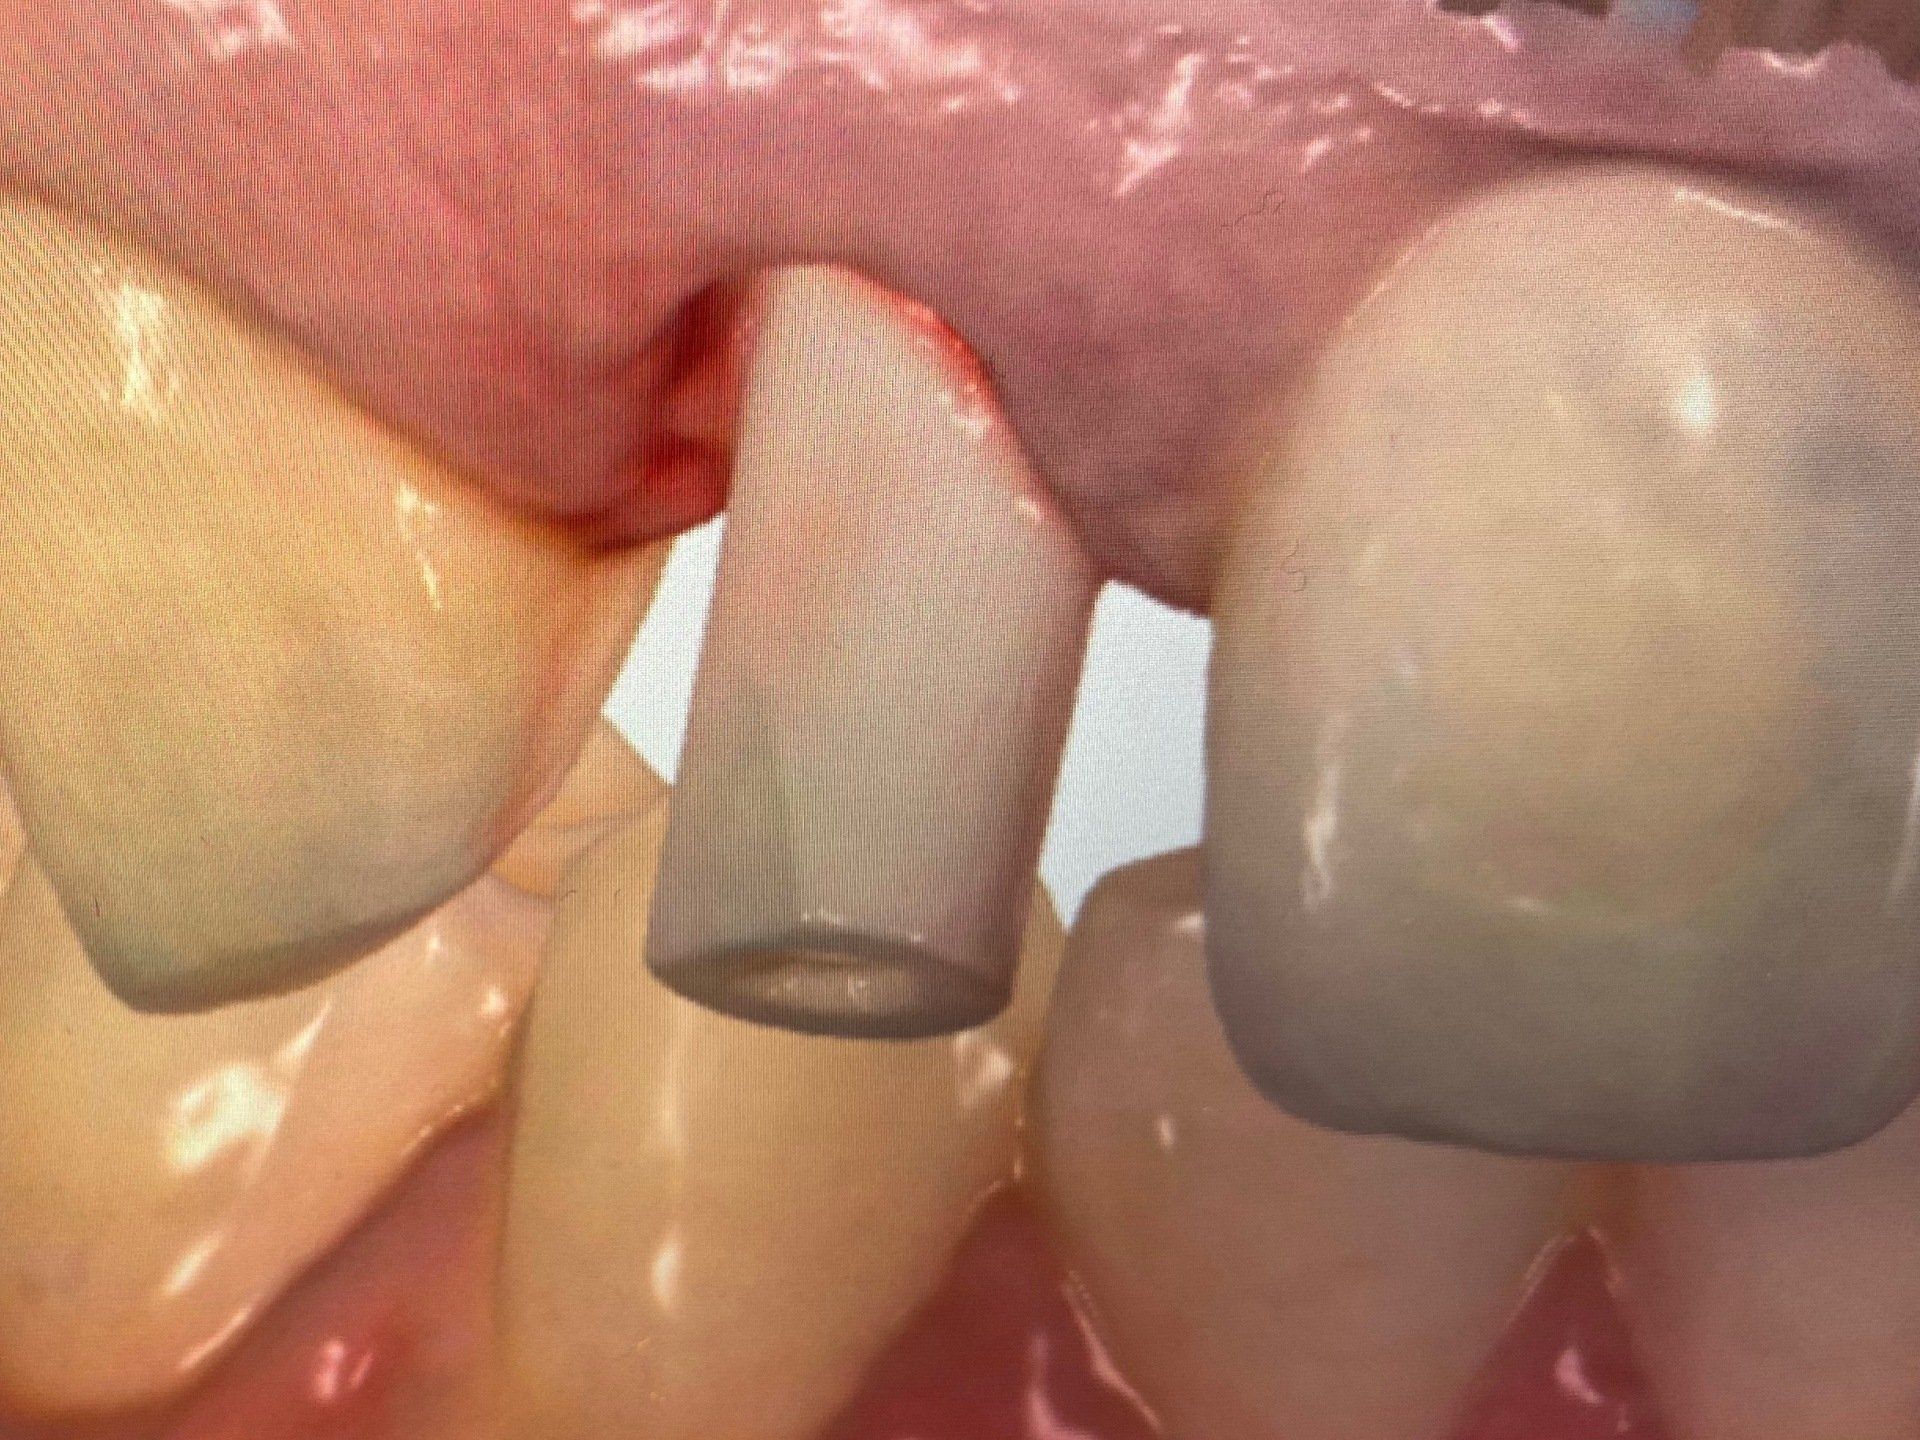

Provisorische Versorgung mit gefrästem Kunststoffprovisorium:

Fall 1:

Verschraubung des Kunststoffprovisoriums am selben Tag